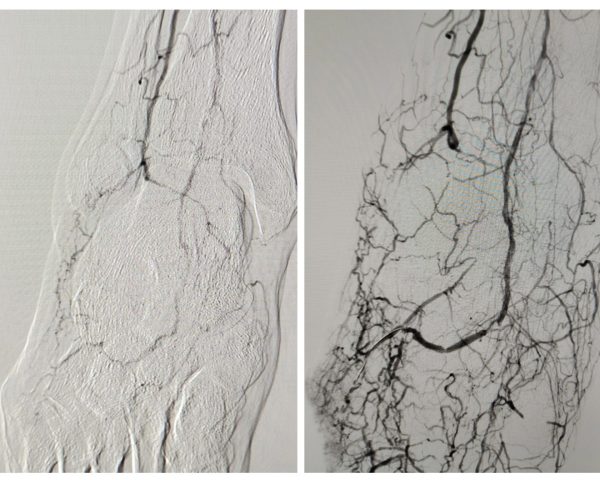

El Eco-Doppler de control mostró:

- Curva espectral trifásica mantenida desde femoral hasta tibial anterior.

- Flujo directo en arteria pedia hasta la arcada plantar, irrigando la zona previamente isquémica.

- Disminución del PAT a 84 ms (Clase 1, perfusión adecuada).